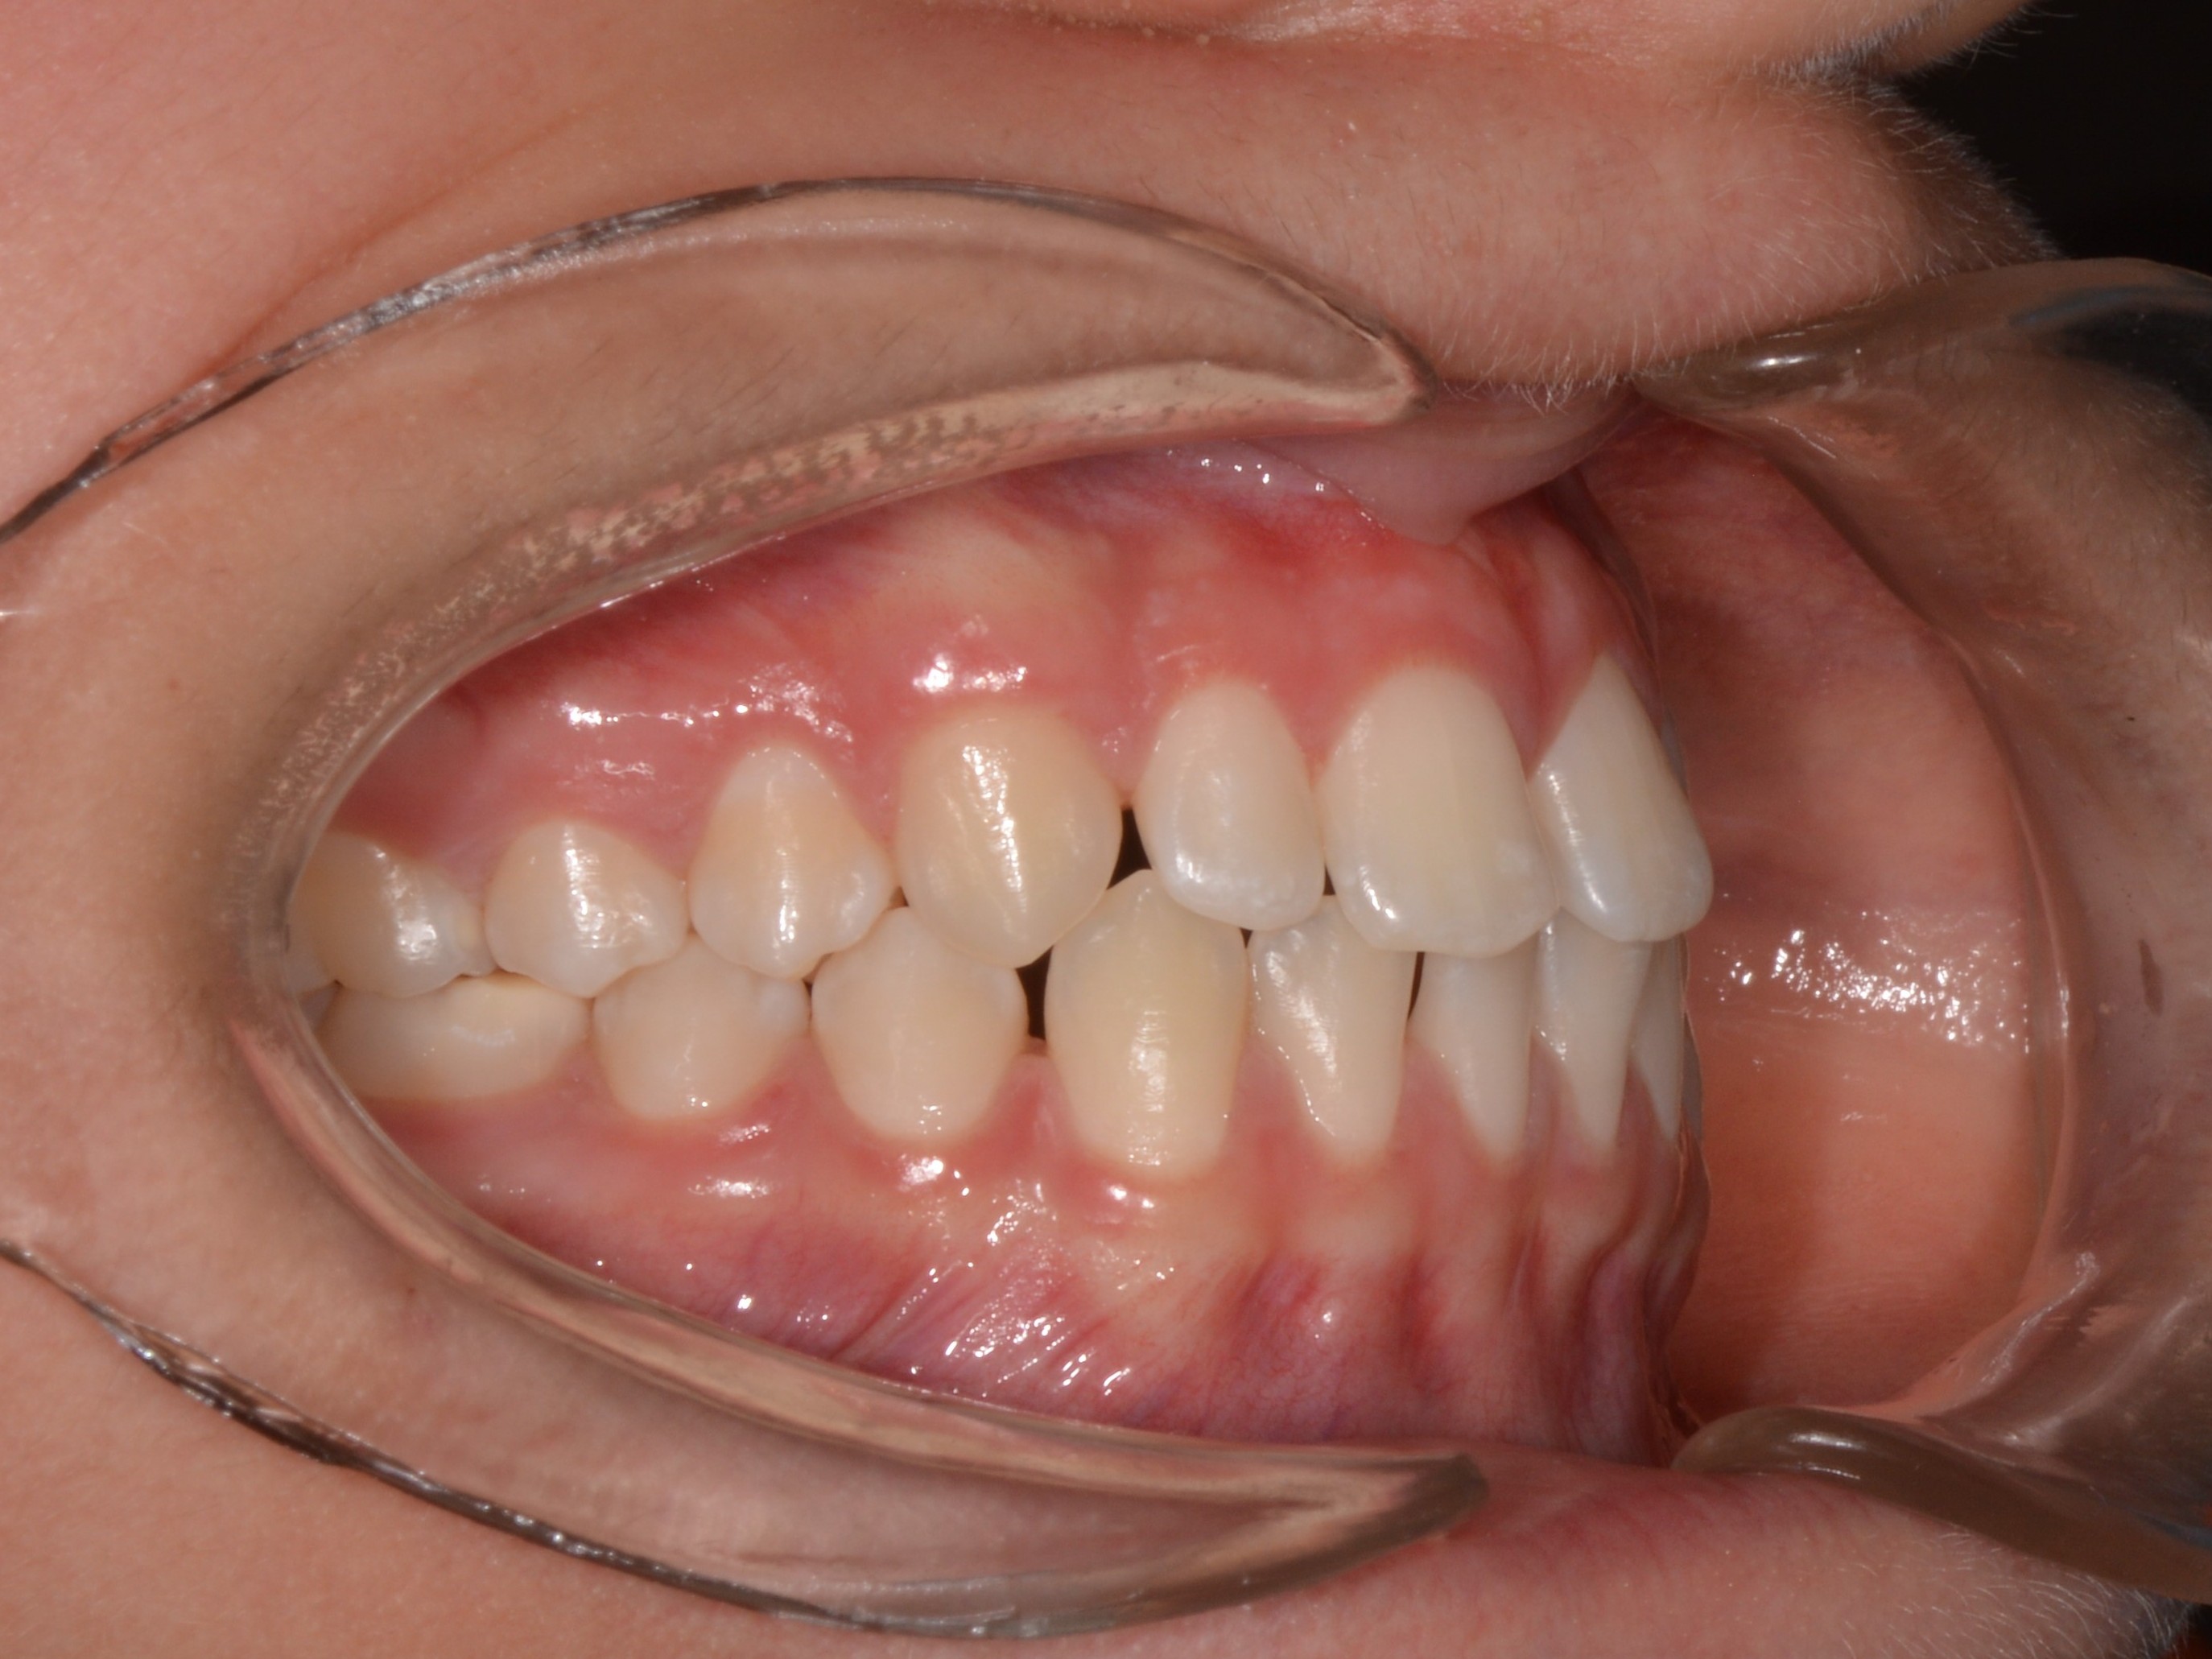

Femmina, 13 anni

Classe III

• Diastema

• Deviazione della linea mediana mascellare

• Archi stretti

• Morso aperto